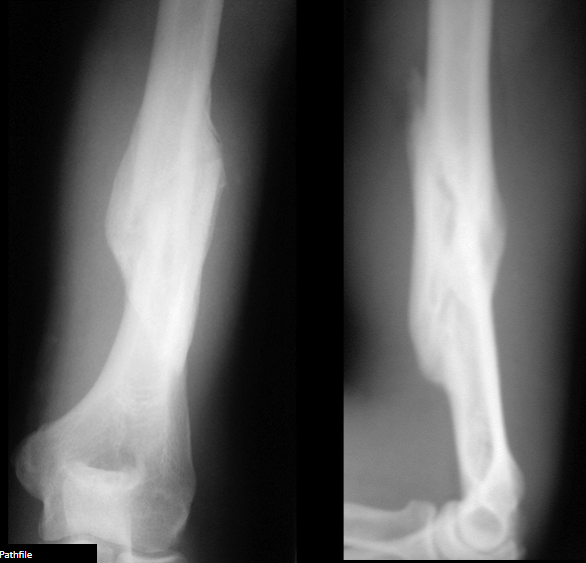

5

What is the diagnosis for the fracture of the radius and the causative mechanism?

A

Greenstick fracture

Angular/shear force (bending)

6

What is the diagnosis for the fracture of the ulna and the causative mechanism?

Torus fracture

Compressive/axial force